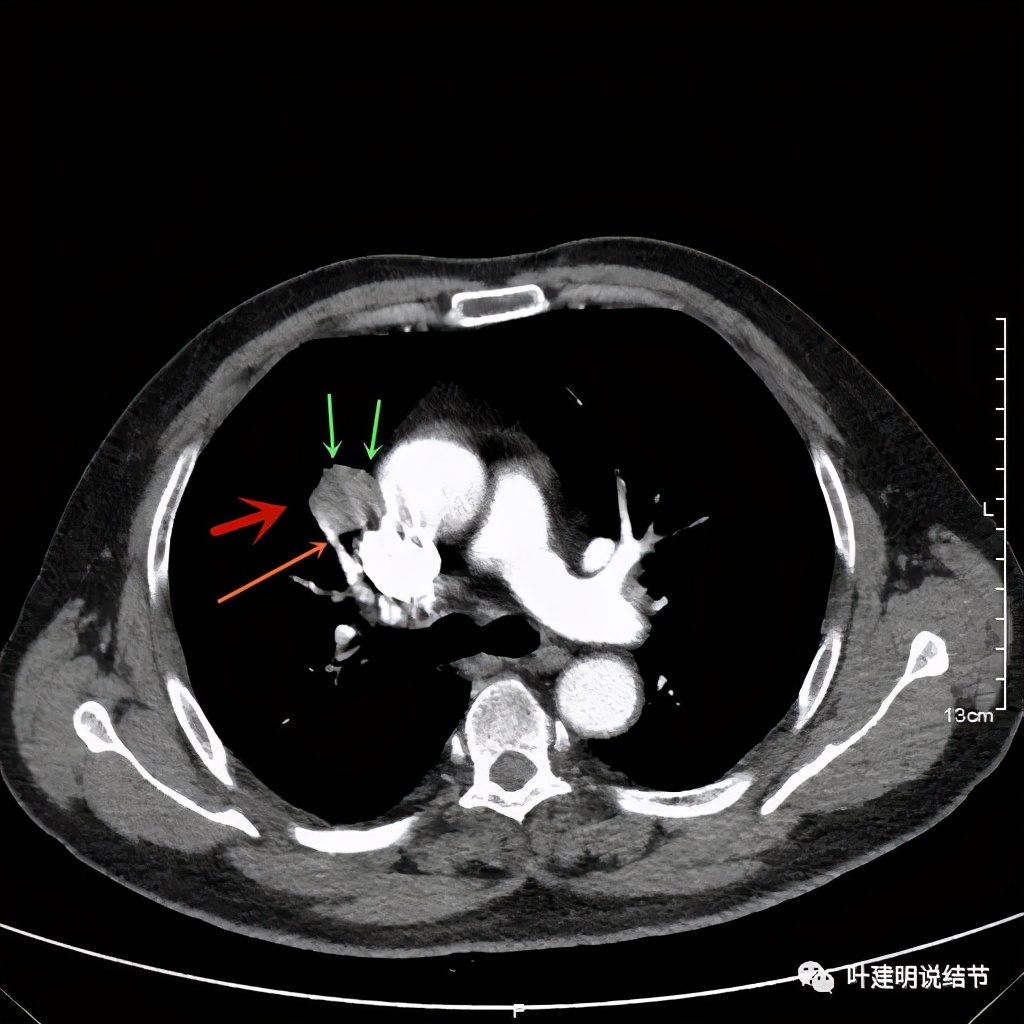

可见右上叶占位,我们现在知道了结果以后回头看,发现病灶的边缘在各个层面都是过于光滑(绿色箭头所示)。血管紧贴病灶边走行(桔色箭头所指),是不是有侵犯看不清楚,若是靶扫描加重建可能会更清楚点。支气管感觉也是贴着病灶走,但有的层面是不是截断,也不看的不太清楚。有的层面见局部有点状高密度(蓝色箭头所指),是不是错构瘤的局部钙化呢?若是纵隔窗又是如何?

上图示病灶密度不均,但边缘过于光滑(绿色);支气管似有截断(粉色);局部有点状钙化(蓝色)

上图也示病灶密度不均,但边缘过于光滑(绿色);支气管似有截断(粉色);局部有点状钙化(蓝色)

病灶在上图层面似见支气管也是贴壁的。那么增强后又是如何呢?